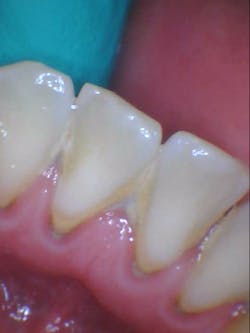

- Additional caries were noted on nos. 10, 11, 14, 26, 27, and 29—primarily facial/buccal caries (figures 3–8)